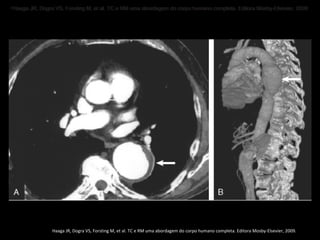

• Haaga JR, Dogra VS, Forsting M, et al. TC e RM uma abordagem do corpo humano completa. Editora Mosby-Elsevier, 2009 ..

• Haaga JR, Dogra VS, Forsting M, et al. TC e RM uma abordagem do corpo humano completa. Editora Mosby-Elsevier, 2009

Haaga JR, Dogra VS, Forsting M, et al. TC e RM uma abordagem do corpo humano completa. Editora Mosby-Elsevier, 2009.